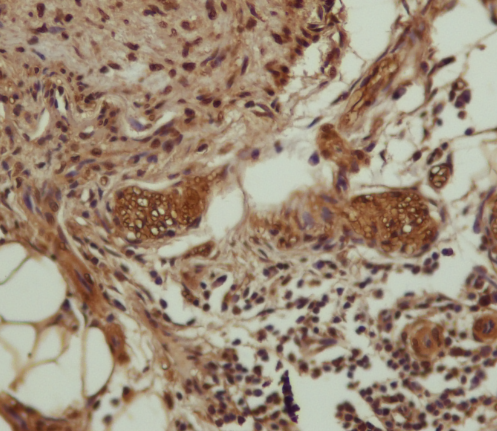

请做过免疫组化的进来鉴定一下我的ICH图片~ 已有5人参与

免疫组化 |